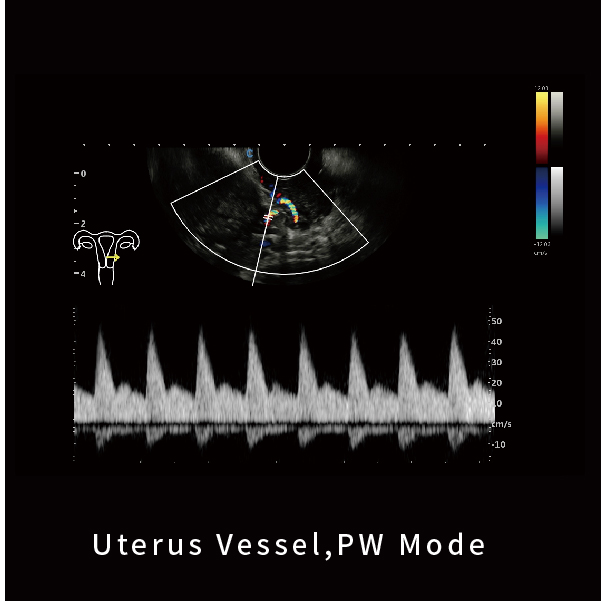

子宫血流,PW模式